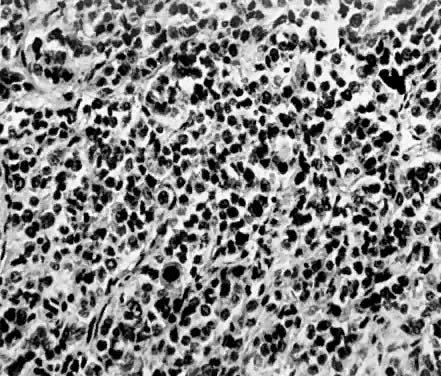

Endometrial stromal sarcomas are composed of monotonous sheets of cells with basophilic nuclei and scant cytoplasm. These cells are usually round with dark-staining nuclei and resemble cells of the endometrial stroma as opposed to the long, thin, tapered cells of the uterine musculature21 (Fig. 4). Endometrial glands may or may not be present, and their absence may be the result of either an atrophic endometrium or replacement by the stromal sarcoma. The endometrial stromal sarcoma may invade the myometrial smooth muscle to various degrees (Fig. 5).

Fig. 4. Endometrial stromal sarcoma composed of nests of uniform cells with round nuclei separated by a delicate stroma. Several abnormal mitoses are present (H&E, × 350)